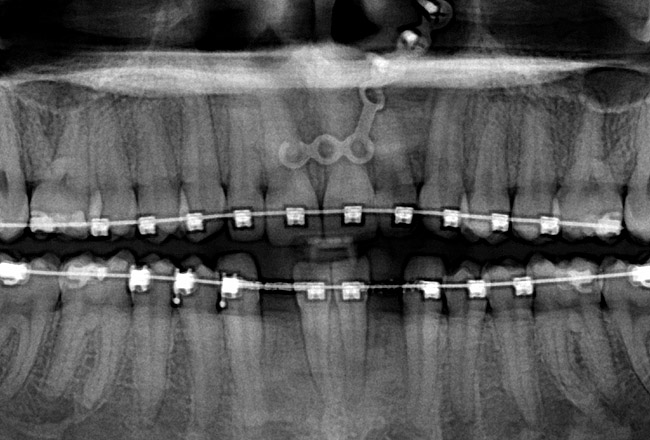

Fig 24 (through Fig 26). A 50-year-old female concerned about appearance and bite. Jackscrew appliance was placed after 6 months of orthodontic alignment.

Figure 24

Fig 25. A 50-year-old female concerned about appearance and bite. Jackscrew appliance was placed after 6 months of orthodontic alignment.

Figure 25

Fig 26. A 50-year-old female concerned about appearance and bite. Jackscrew appliance was placed after 6 months of orthodontic alignment.

Figure 26

Fig 27. Patient was missing tooth No. 11 and had A-P and transverse maxillary deficiencies with anterior and left posterior crossbites. Bite was opened with glass ionomer cement. Single-tooth osteotomies were performed on teeth Nos. 6 and 12 and multiple-tooth osteotomies were completed on teeth Nos. 3 to 4, 7 to 10, and 13 to 14.

Figure 27

Fig 28. Corticotomies were also performed on Nos. 7 to 10 segment. Postsurgery 21 days.

Figure 28

Fig 29 (through Fig 32). Jackscrews were activated 0.5 mm/day after 5-day latency period. Note pure translation of segments without tipping. Result 8 months postsurgery. Tooth No. 12 was converted to a canine, and an implant was placed in regenerate bone. Note amount of alveoloskeletal correction and increase in volume of maxillary arch. Also note the amount of protraction of maxillary anterior segments while anchorage was maintained in posterior segment. Restorative dentist: Michael E. Carter, DDS.

Figure 29